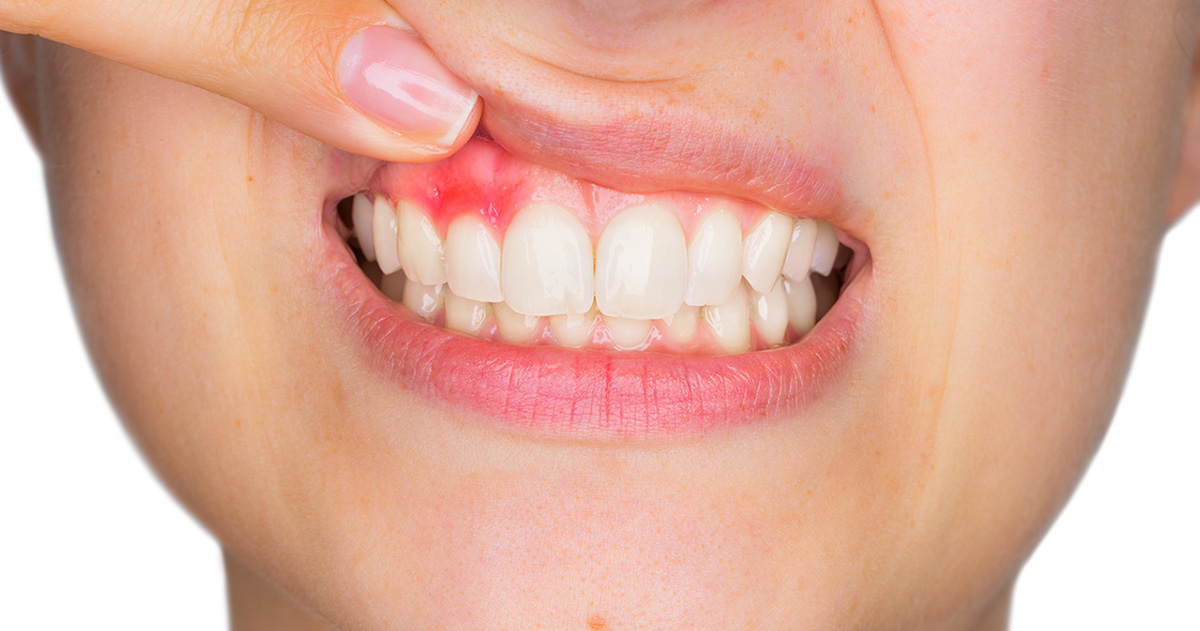

4 best treatments for a cracked tooth You can get a cracked tooth because of any reason. This includes grinding teeth at night, chewing hard food, and much more. When you notice this, the key is to seek help immediately. If you leave it for too long, the issue will get worse. Cracked teeth require…